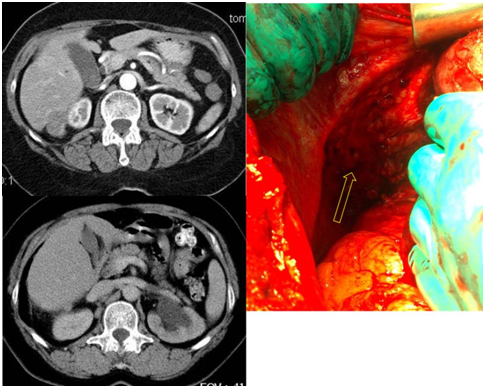

Figure 5 Implants of abdominal surface of the right diaphragm on CT scan and intraoperative image.

Figure 6 Implants of liver fibrous capsule (Glisson's capsule) on CT scan and intraoperative image.